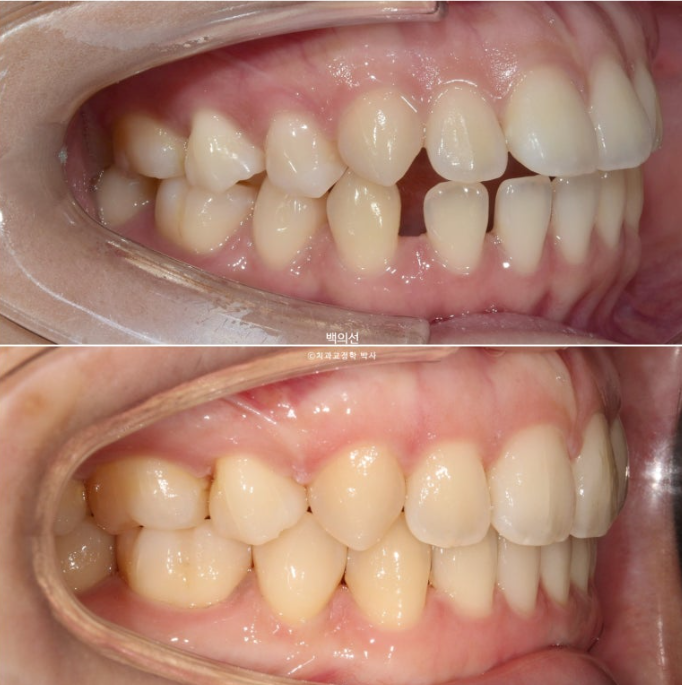

23.01~25.07

맞아진 중심선과 개선된 앞니 개방교합. 이제 면 편하게 끊어 드실 수 있겠어요.

어금니 교합이 기존 3급에서 정1급 교합관계로 바뀌었습니다.